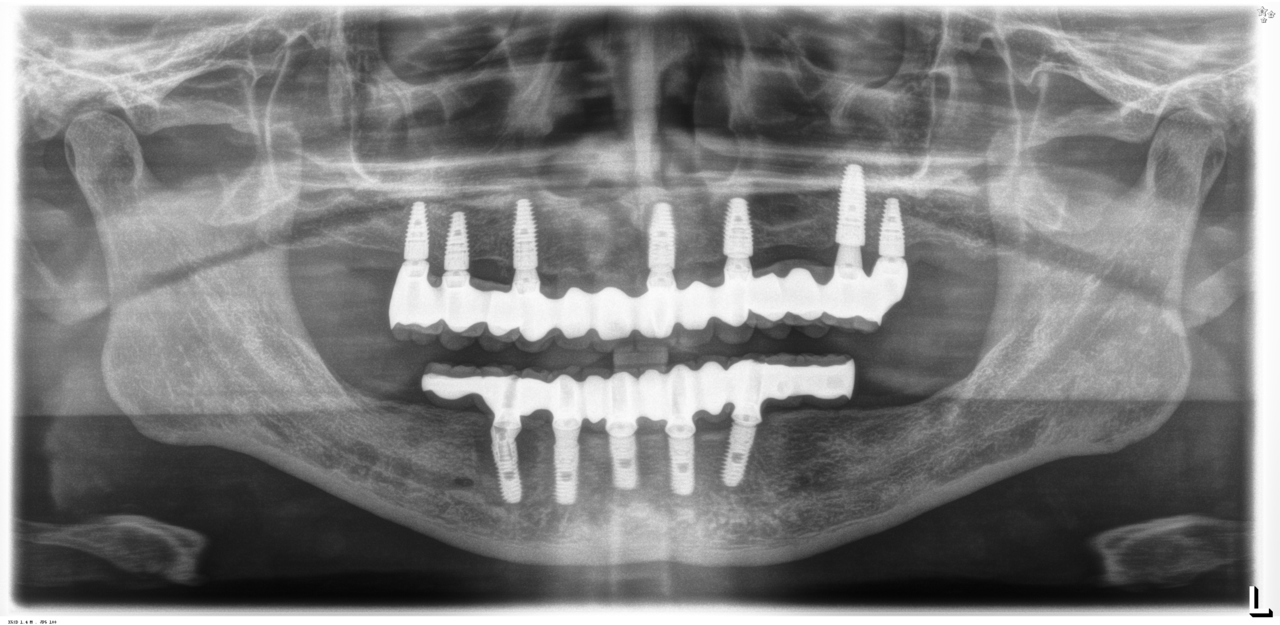

完成後のレントゲン写真

最終的な被せ物を装着した状態のレントゲン写真。

(今回は下顎ですが、その前に上顎は治療済みです。)

【下顎インプラント8本で14本の歯を回復するスクリュー固定タイプ】

インプラント手術:250,000円×8本=2,000,000円

静脈内鎮静法:0円

既製アバットメント:90,000円×8個=720,000円

メタルボンド:130,000円×14本=1,820,000円

マルチアバットメント:25,000円×8個=200,000円

連結料:10,000円×13カ所=130,000円

仮歯:50,000円×8本=400,000円

ポンティック:10,000円×6本=60,000円

ラジオグラフィックガイド(11本):22,000円

埋入ガイド(8本):73,000円

総額:5,425,000円+税